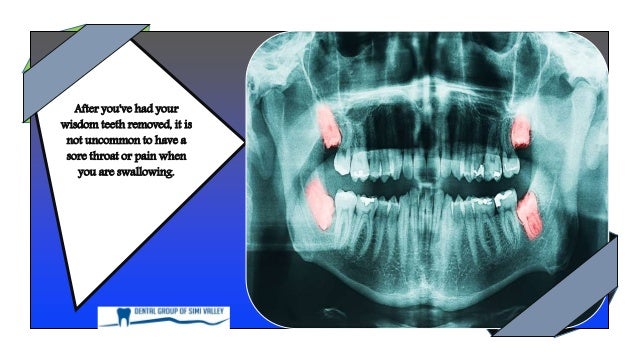

Ear and throat pain after wisdom teeth removal. After youve had your wisdom teeth removed it is not uncommon to have a sore throat or pain when you are swallowing. Your muscles will get swollen so the act of swallowing could become painful. You might even have stiffness in your jaw muscles which is completely normal.

It is not uncommon to have some ear soreness after wisdom teeth extraction. It most likely due to muscle and TMJ strain during the procedure. The ear pain after wisdom teeth removal is normal.

After the extraction process some inflammation is to be expected in the area. This inflammation can cause ear pain which is normal for some days during the healing process. In this time steroids and painkillers usually get prescribed to decrease inflammation and relieve the pain which help to aid the healing process.